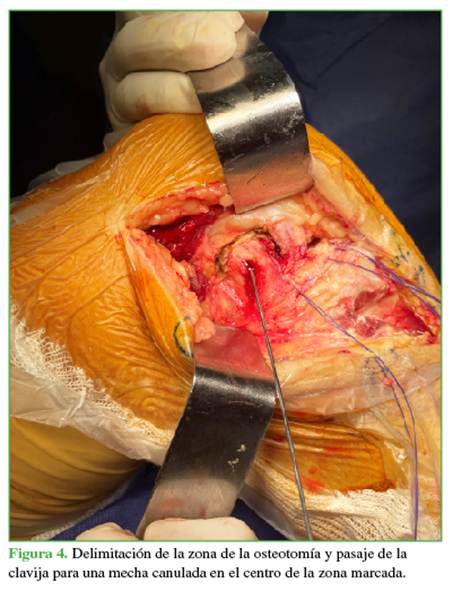

A continuación, se amplía el abordaje con la osteotomía del epicóndilo lateral, se localizan, en el sector epicondíleo, las inserciones del ligamento colateral lateral y del tendón poplíteo, se los individualiza (Figura 3), se delimita con electrobisturí un área rectangular de aproximadamente 3 cm de largo x 2 cm de ancho abarcando ambas inserciones, esto permite tener un taco óseo de mayor tamaño sin correr el riesgo de que se fracture en el momento de la osteosíntesis.

Además, al incluir la inserción del poplíteo, aumenta el área de visualización.2 En el centro del marcado, se perfora con una mecha canulada de 3,5 en dirección de 30° a proximal y 30° a anterior, dejando preparado el taco óseo para su reinserción (Figura 4).